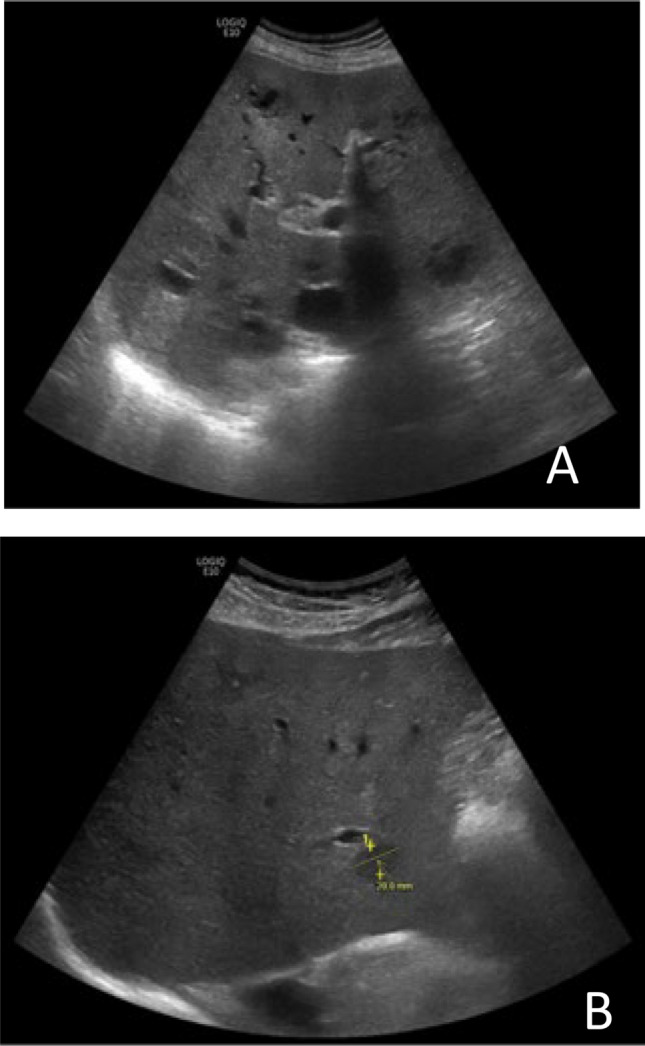

Non-O1/non-O139 Vibrio cholerae (NOVC) strains are a distinct group of Vibrio cholerae that do not cause epidemic cholera. NOVC infections usually cause mild forms of gastroenteritis, and rarely severe (extra)intestinal infections, mostly affecting immunocompromised patients. Here, we describe the clinical course of a patient with NOVC bacteremia causing multiple liver abscesses, after drinking from a freshwater well in a non-coastal area. This case highlights the potential of a V. cholerae strain, that is phylogenetically distinct from the current pandemic cholera strain, to cause severe extra-intestinal infections, including liver abscesses.